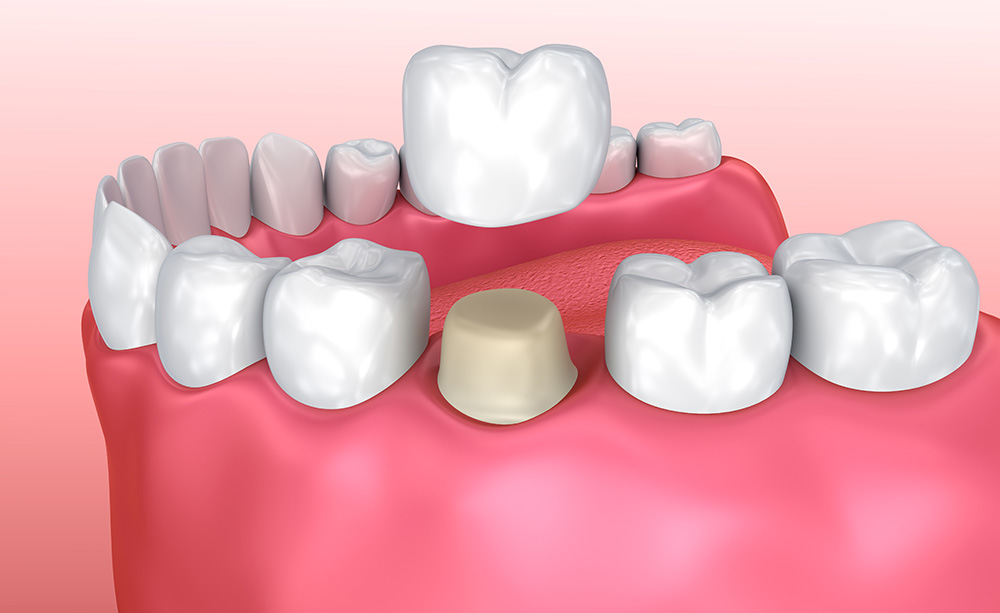

Coronas. Fabricadas en distintos materiales (cerámica, metal-cerámica o completamente metálica) cubren y restauran la totalidad del diente. Se realizan a medida y de manera exclusiva en el laboratorio.

Colocación de la Corona

Este tipo de rehabilitación tiene como finalidad la reposición de las ausencias dentarias utilizando los dientes del paciente como punto de anclaje fijo para la futura prótesis. Para tal fin, será necesario llevar a cabo la correcta preparación de los dientes que servirán de pilar mediante un tallado que varía en función de la forma y el tamaño del diente. Si bien es cierto que en ocasiones los pacientes refieren tras el tratamiento cierto grado de sensibilidad frente a determinados estímulos, como los cambios de temperatura. Cuando tales molestias persisten en el tiempo, puede ser necesaria la realización de una endodoncia. Rehabilitaciones complejas por medio de una prótesis fija dento-soportada pueden requerir un período de adaptación en el que el paciente podrá percibir una mayor cantidad de salivación e incluso llegar a morderse la lengua o las mejillas. Como en cualquier tratamiento odontológico, resulta indispensable acudir periódicamente a las correspondientes revisiones para poder determinar posibles problemas, como movimiento de la/-s corona/-s por descementado de la/-s misma/-s o fracturas de la cerámica como consecuencia de fuerzas masticatorias intensas, entre otros.